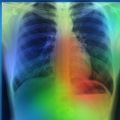

Oxford to collaborate on AI algorithms to help predict COVID-19 severity in patients

Research

Science

Coronavirus